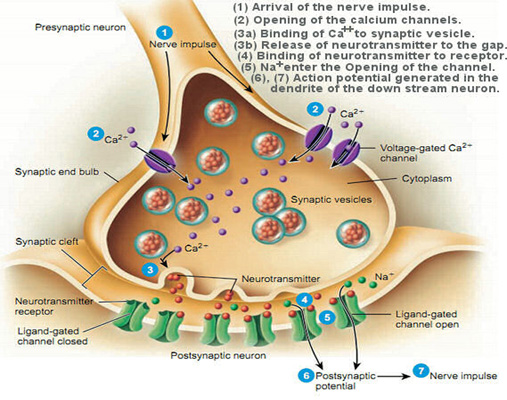

Our bodies are electromagnetic. This is why our brains work and why our heart beats and our muscles contract. As Michio Kaku, CUNY physicist, futurist, and author says, “Our brains are milliwatt transmitters.” Nature, the premier publication in science, notes: “There are striking analogies between signaling networks in biological systems and electronic circuits.”

Electromagnetic fields of all kinds (radiofrequency/microwave, dirty electricity) knock calcium ions off the cell membrane. This accounts for the wide variety of effects seen with exposure to smart meters because calcium acts like a neurotransmitter. Thus, your heart, your gut, your brain, your muscles, and your hormones can be affected. In general, the first place that is harmed is the place where you have the least resistance. Over time, various other organ systems will be harmed. We go into this in great detail on our Health: The Science page.

Why do smart meters cause such a vast array of health effects? The effect of EMFs on calcium can explain the vast majority of health effects, first because calcium plays a critical role in the transmission of nerve signals and secondly because calcium is the glue that holds the cell walls together. EMFs can easily knock the calcium ions off the cell membrane.

An excess calcium causes the transmission of unnecessary nerve signals. This accounts for things like heart palpitations, insomnia, and anxiety, and ADD. You can read about this in greater detail on our Health: The Science page, where we have numerous links to research on this phenomenon.

When calcium is pulled off the cell wall, the cell membrane is weakenedâthe cell becomes leaky. Leaky cell walls cause the blood-brain barrier is breached. The blood-brain barrier protects our brain from toxins. A leaky blood-brain barrier is partly responsible for diseases like Alzheimer’s, dementia, and Parkinson’s. Have you ever wondered why we have seen such a huge climb in the rate of Alzheimer's, dementia, and Parkinson’s disease? Have you noticed how the increase correlates with the proliferation of wireless in our society? The background RF radiation has increased 20,000 times since the 1980s! It’s about 15 years into that that we started to see a really big rise in these diseases.